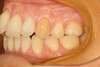

Rédicive d'un traitement dans l'enfance repris avec des gouttières